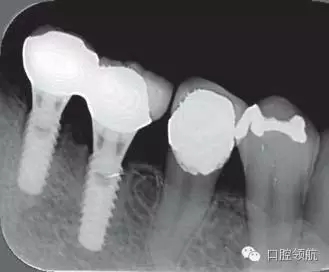

2005年4月時(shí),可見(左下第6顆牙) 部的種植體達(dá)到第4螺紋,(左下第7顆牙)的種植體周圍觀察到位于第3螺紋的頸部進(jìn)行性骨吸收(圖4)。到2009年9月時(shí),骨吸收像的周圍有了明顯的骨密度增加影像(圖5)。

圖4 (左下第6顆牙)的種植體達(dá)到第4螺紋, 7 的種植體達(dá)到第3螺紋的頸部進(jìn)行性骨吸收現(xiàn)象(2005年4月)。

圖5 骨吸收像的周圍有了明顯的骨密度增高影像(2009年9月)